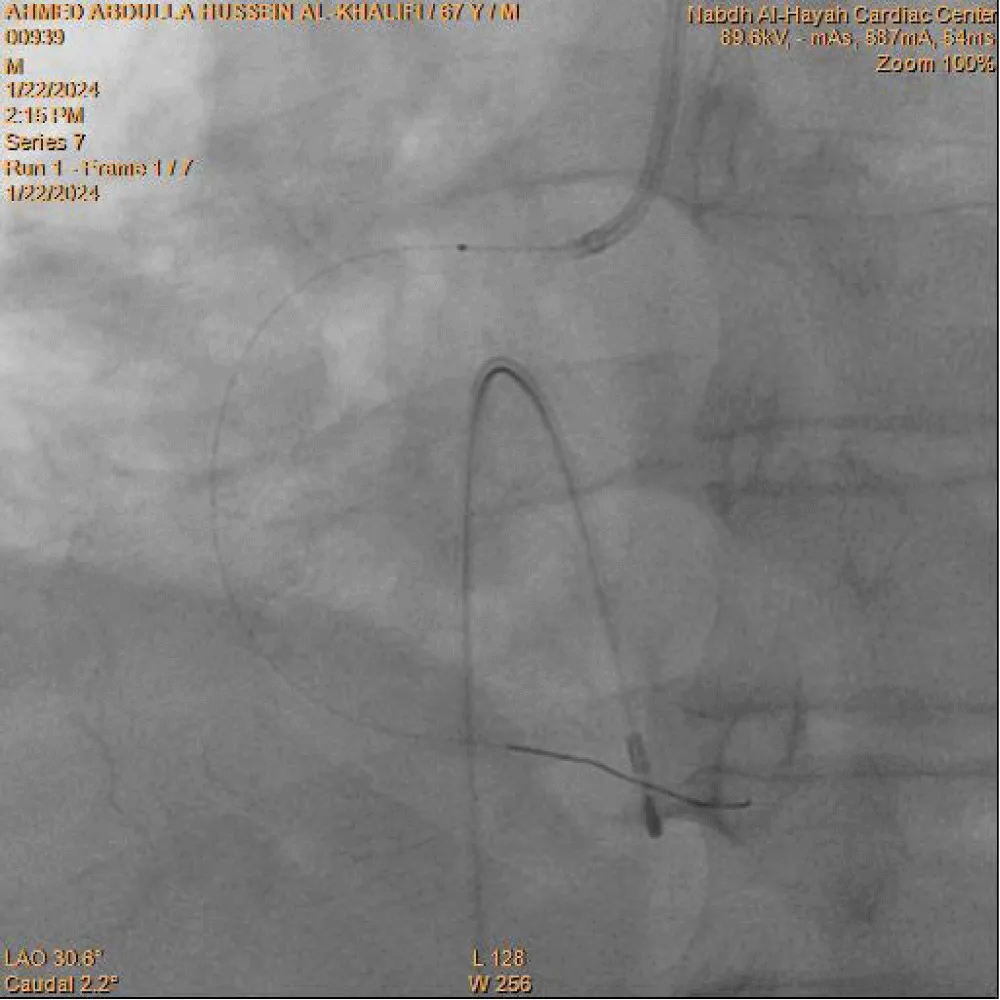

Primary percutaneous coronary intervention (PCI) was decided, and the catheterization laboratory team was immediately activated. A trans-femoral venous approach was used for temporary pacemaker insertion, which was successfully established at a fixed rate of 60 beats/min. An initial attempt at right radial artery puncture for coronary angiography was unsuccessful; therefore, crossover to the right femoral artery was performed.

Coronary angiography was carried out using a 6-Fr diagnostic left Judkins catheter, which revealed an atherosclerotic left coronary system. A right Judkins guiding catheter was then used to cannulate the right coronary artery (RCA), demonstrating total occlusion of the proximal RCA with a high thrombus burden. The occluded segment was successfully crossed with a 0.014-inch BMW PTCA floppy guidewire. Limited thrombus aspiration was achieved after five passes using a 6-Fr Export aspiration catheter (Medtronic), as shown in Figure 3. Control angiography of the RCA after thrombus aspiration demonstrated TIMI I flow. Subsequently, a 1.25 × 10 mm Sprinter balloon (Medtronic Inc.) was advanced over the guidewire for balloon predilatation. Upon reaching the proximal RCA, three radiopaque markers were visualized instead of the expected two (Figure 4). This immediately raised suspicion of a device fracture. Careful inspection of the Export catheter, which had just been withdrawn from the guiding catheter and was lying on the table, confirmed loss of its distal tip. This represented a precarious situation, with a thrombogenic broken catheter fragment retained within a thrombus-laden coronary artery and loss of operator control over the fragment.